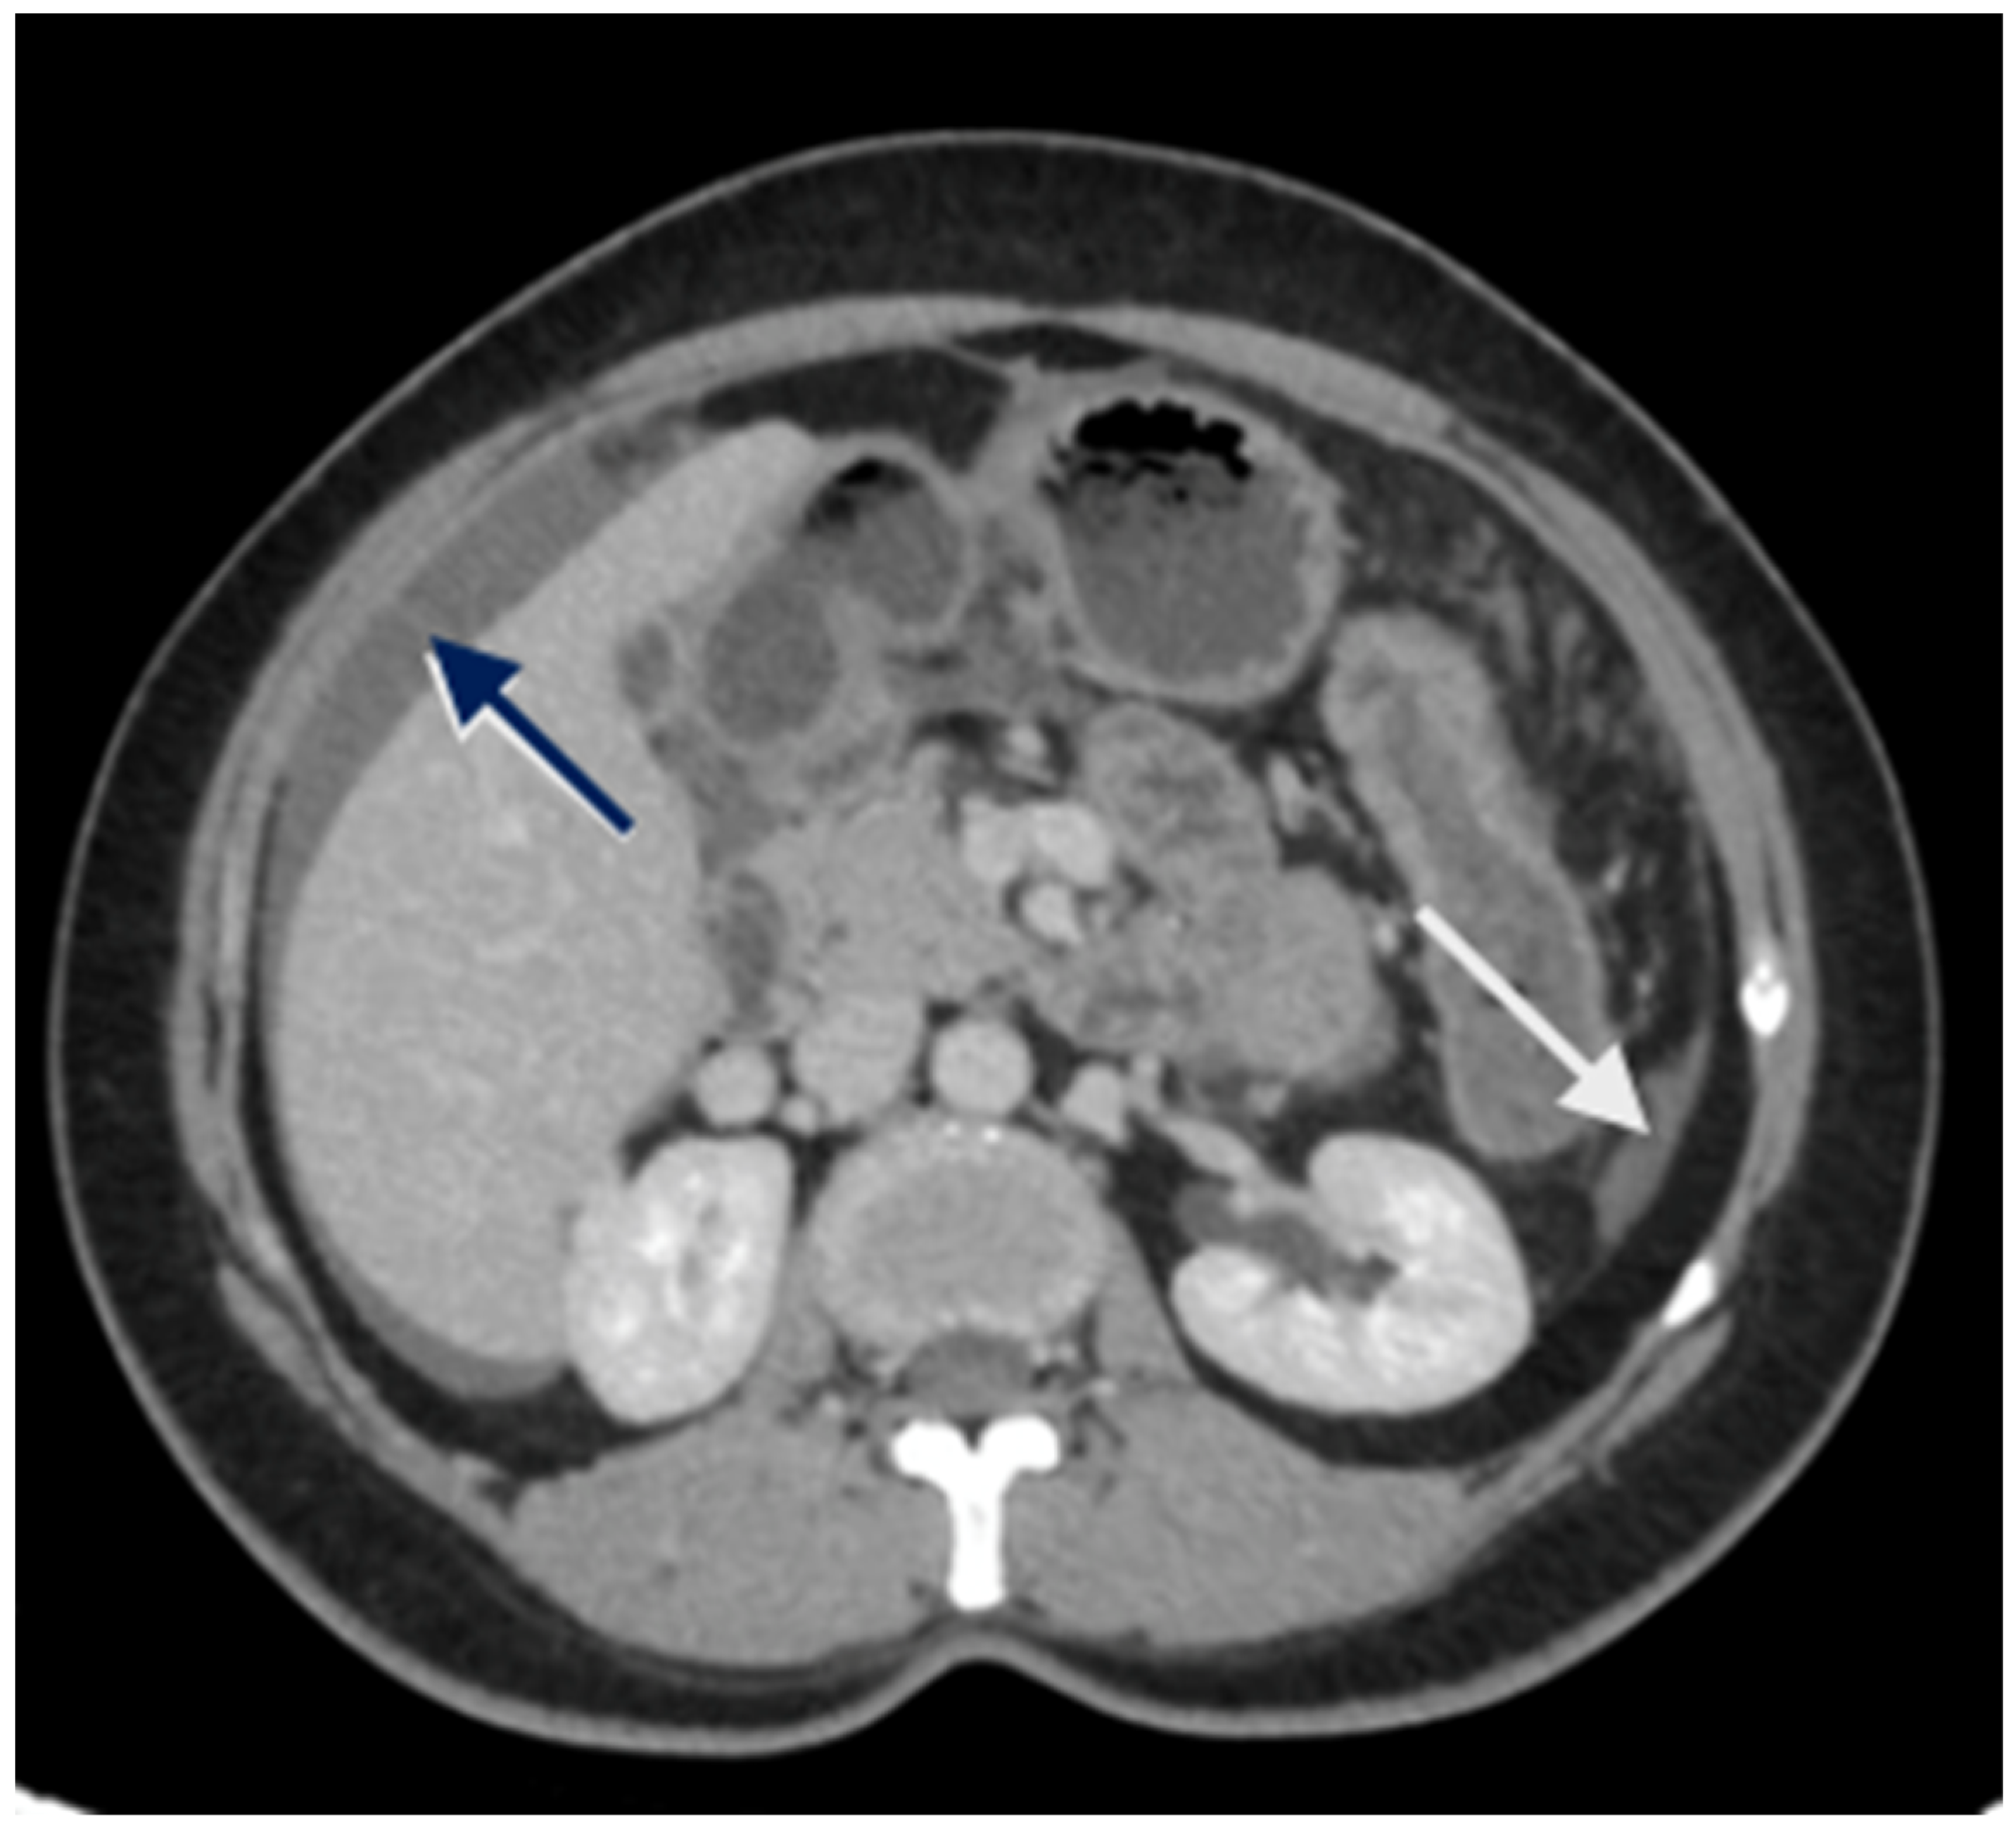

Loculated fluid collections adjacent to the liver, indentation of the liver surface, and fluid in the sub-hepatic region are some pre-emptive signs of underlying peritoneal disease (Figure 2). A contrast-enhanced MRI of the abdomen and pelvis with a dedicated protocol for the detection of peritoneal disease is being used at several centers and has shown to be more accurate in predicting the disease extent [51,52].

Figure 2.

CT scan showing nodular peritoneal deposit on the subphrenic peritoneum (white arrow); loculated fluid collection (blue arrow).